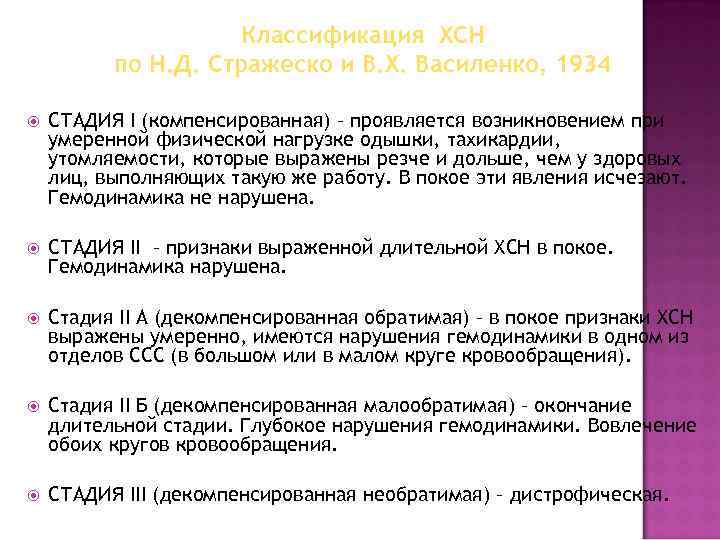

Классификация ХСН по Н. Д. Стражеско и В. Х. Василенко, 1934 СТАДИЯ I (компенсированная) – проявляется возникновением при умеренной физической нагрузке одышки, тахикардии, утомляемости, которые выражены резче и дольше, чем у здоровых лиц, выполняющих такую же работу. В покое эти явления исчезают. Гемодинамика не нарушена. СТАДИЯ II – признаки выраженной длительной ХСН в покое. Гемодинамика нарушена. Стадия II А (декомпенсированная обратимая) – в покое признаки ХСН выражены умеренно, имеются нарушения гемодинамики в одном из отделов ССС (в большом или в малом круге кровообращения). Стадия II Б (декомпенсированная малообратимая) – окончание длительной стадии. Глубокое нарушения гемодинамики. Вовлечение обоих кругов кровообращения. СТАДИЯ III (декомпенсированная необратимая) – дистрофическая.

Классификация ХСН по Н. Д. Стражеско и В. Х. Василенко, 1934 СТАДИЯ I (компенсированная) – проявляется возникновением при умеренной физической нагрузке одышки, тахикардии, утомляемости, которые выражены резче и дольше, чем у здоровых лиц, выполняющих такую же работу. В покое эти явления исчезают. Гемодинамика не нарушена. СТАДИЯ II – признаки выраженной длительной ХСН в покое. Гемодинамика нарушена. Стадия II А (декомпенсированная обратимая) – в покое признаки ХСН выражены умеренно, имеются нарушения гемодинамики в одном из отделов ССС (в большом или в малом круге кровообращения). Стадия II Б (декомпенсированная малообратимая) – окончание длительной стадии. Глубокое нарушения гемодинамики. Вовлечение обоих кругов кровообращения. СТАДИЯ III (декомпенсированная необратимая) – дистрофическая.